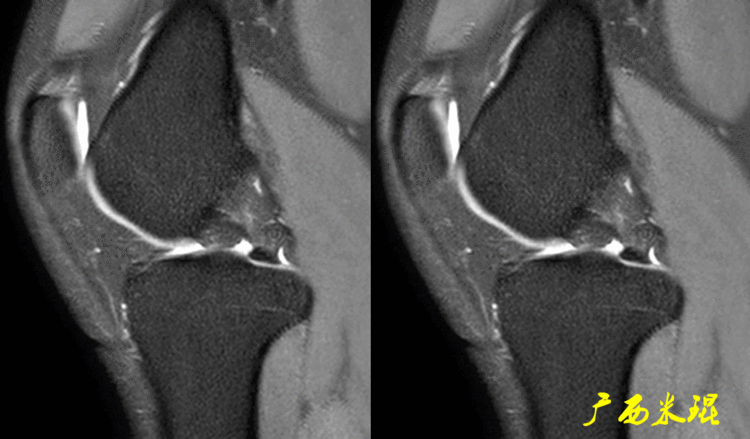

(2)隐窝隐窝是半月板后角与关节囊之间的正常凹陷,与体位等有关,可有可无,一般情况下积液越多隐窝越大,有上下之分,下面这张MR矢状位片见到的是上隐窝,紧贴半月板、光滑、不连通是其特点,也是鉴别要点。

下面这张MR矢状位片见到的是下隐窝,也紧贴半月板、光滑、不连通。

隐窝需要与半月板囊肿鉴别,下面这张MR矢状位片见到的是内侧半月板后角损伤并囊肿形成,与隐窝是有明显区别的。

隐窝还需要与半月板关节囊分离鉴别,下面这张MR矢状位片见到的内侧半月板后角与关节囊完全分离,周围水肿,胫骨内侧平台后方骨水肿;而隐窝是不会连通的。